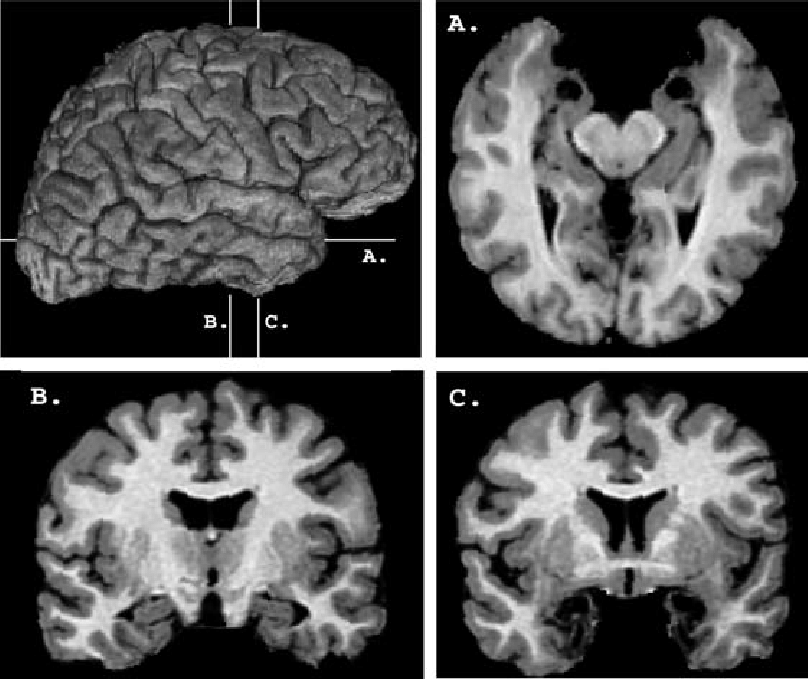

James Papez 1937 limbiska systemet

Idag vanligt att Àven inkludera:

Begreppet limbiska systemet kritiseras idag eftersom det bygger pĂ„ den förenklade âreptilhjĂ€rnanâ-idĂ©n och saknar förklaringskraft; modern forskning betonar istĂ€llet distribuerade nĂ€tverk för emotion.